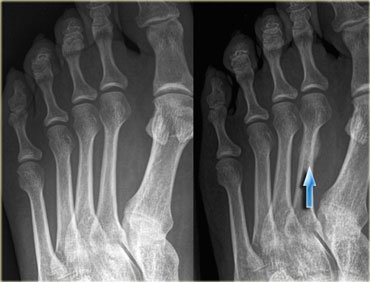

Stress fractures are notoriously difficult to diagnose. Superficially, there is typically swelling, pain, and redness. In the early stages on x-ray, a very faint line is present, this faint line can be confused with blood vessel marks in the bone or just overlooked all together. At 2 weeks the bone starts to display signs of bone heeling, this is evident by fluffy bone growth around the fracture site- called callus formation. When the callus formation is visible a stress fracture is much easier to diagnose. If it is uncertain if there is a stress fracture, an MRI, CT, or bone scan can be done, these radiology studies make it very ease to identify any abnormalities in the bone.

- Callus formation gives away the presence of the stress fracture